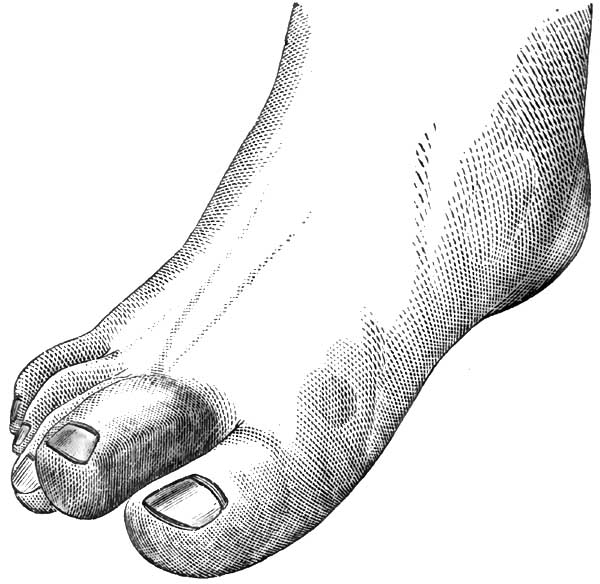

| 9. | SYPHILITIC DACTYLITIS, FROM BUMSTEAD |

| 10. | THE SAME AS FIG. 9 |

| 11. | SERRATIONS OF NORMAL INCISOR TEETH |